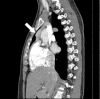

Primary hyperparathyroidism (PHPT) is a hypercalcemia disorder with inappropriately normal or increased serum parathyroid hormone (PTH) levels resulting from excessive secretion of PTH from one or more of the parathyroid glands. PHPT is uncommon in infants and children, with an estimated incidence of 2-5 cases per 100,000 persons. Patients with PHPT usually present with bone pain, urolithiasis, or nephrolithiasis, as well as nonspecific symptoms such as fatigue and weakness. Asymptomatic hypercalcemia may also be detected incidentally. Only a few cases of pediatric PHPT have been reported in Korea. We present three patients (a 9-year-old girl, a 14-year-old boy, and a 14-year-old girl) with PHPT who manifested variable clinical features of hypercalcemia. The first and second patients each had a parathyroid adenoma and presented with abdominal pain caused by pancreatitis and a ureter stone, respectively. The third patient had an ectopic mediastinal parathyroid adenoma and presented with gait disturbance and weakness of the lower extremities. All of the patients underwent surgical resection of parathyroid adenoma, and their serum calcium levels subsequently normalized without medication.